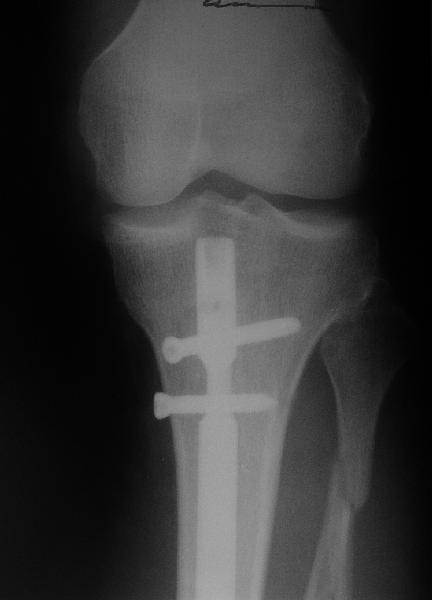

"Ходит с ограниченной нагрузкой на ногу. Направлен из травмпункта по поводу оставшегося смещения отломков. У нас разделилось мнение коллег по вопросу - есть ли необходимость в закрытом интрамедуллярном реостеосинтезе с исправлением оси или только ограничиться динамизацией гвоздя"

Техника введения штифта в дистальные переломы голени отличается от введения в c/3 диафиз. В дистальном отделе штифт надо ввести поглубже и блокировку внизу сделать на все возможные дистальные отверстия. В верхней части короткий штифт создает запас для будущей динамизации.

Одним из идеальных штифтом для лечения дистальных переломов голени является от Synthes Expert Nail, где имеется 4 возможные отверстия для дистальной блокировки, которые в различных направлениях создают дополнительную стабильность.

На снимке сохранен небольшой вальгус, но имеется нормальная аппозиция медиального кортикального слоя и поэтому трудно согласится что здесь имеется неправильно фиксированный перелом. Для идеального сопоставления таких косых переломов надо открывать фокус травмы, но тогда меняется философия фиксации.

Навряд ли рискованные манипуляции в фокусе травмы или ре-остеосинтез улучшит результат кроме рентгенологической картины.

Для предупреждения осложнении можно оставить как есть, потому что всего месяц с момента операции и не видно признаков несостоятельности остеосинтеза.

Отсутствие болей показания к нагрузке и после восстановления движения в суставе через пару-три недели можно сделать динамизацию. За редким исключением, обычно такие “неправильно фиксированные” переломы сростаются в срок.